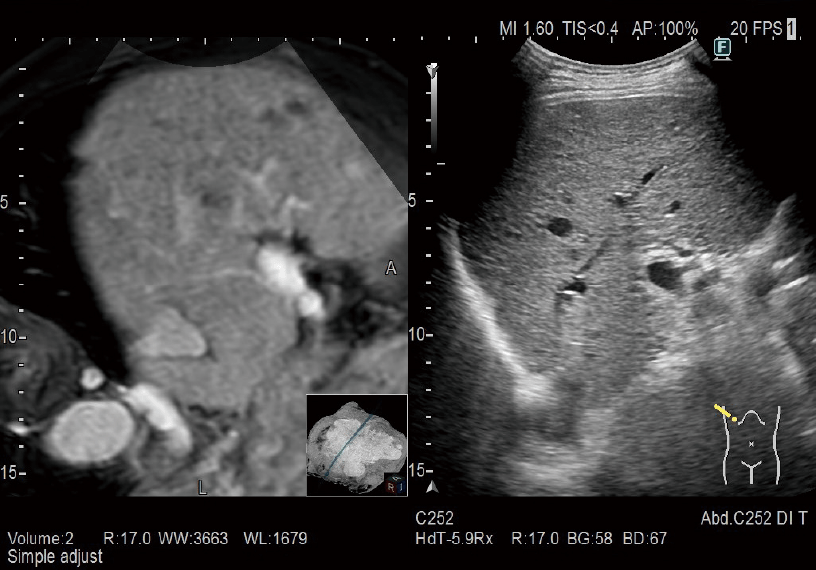

Real-time Virtual Sonography (RVS)

BT/MRG/PET-BT/Ultrason hacim verilerinden oluşturulan MPR görüntüleri, gerçek zamanlı ultrason görüntüleme ile senkronize edilebilir. Karın, Göğüs, prostat ponksiyonunda navigasyon vb. gibi çok çeşitli klinik alanlarda uygulanır.